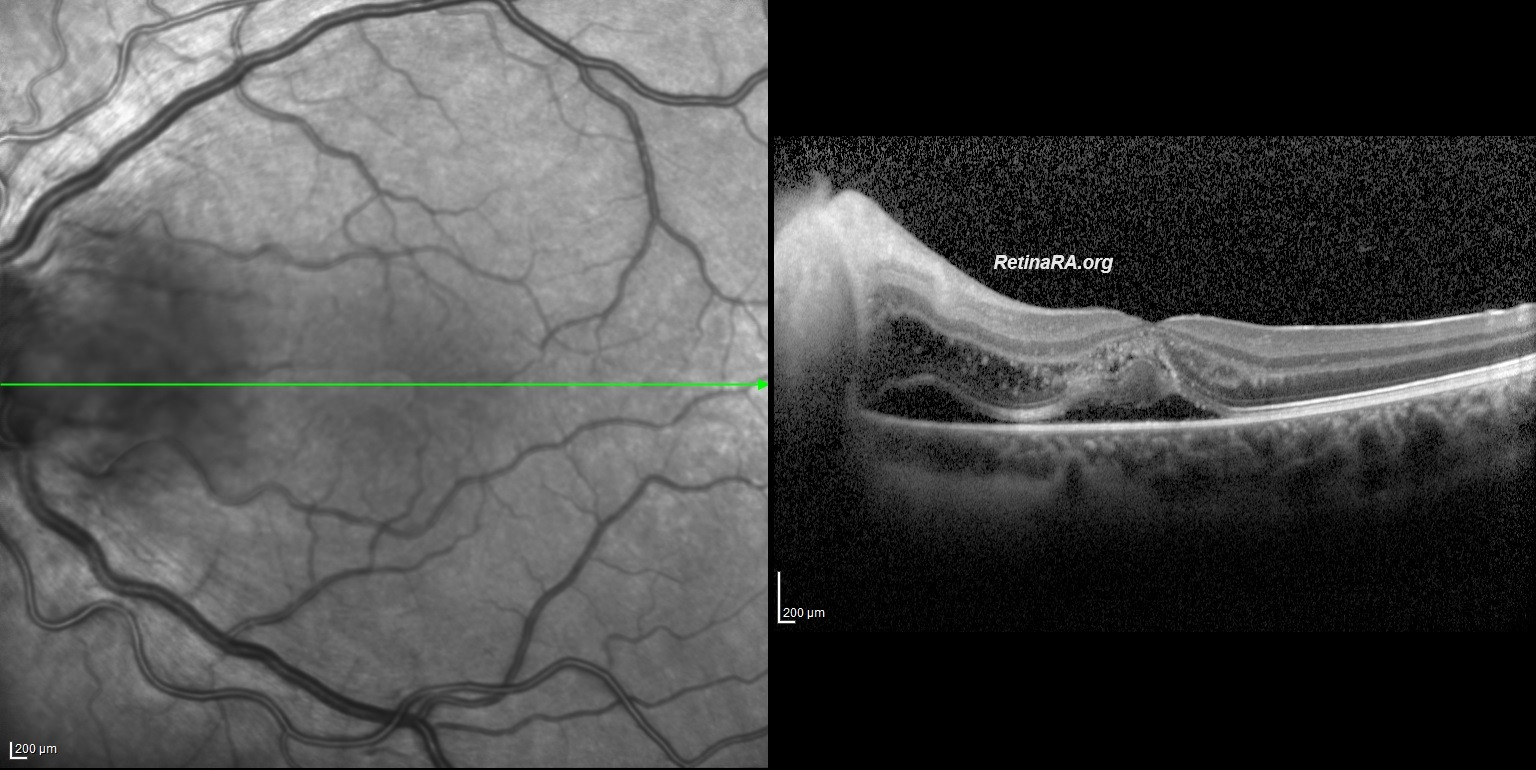

Macular edema was also present. The radial stretching lines seen in multicolor imaging and infrared reflectance imaging indicate fluid accumulation in Henle’s fiber layer. Vertical and horizontal OCT B-scans depict Macular edema with subretinal and intraretinal fluid. *Note that intraretinal fluid and exudate particularly accumulated in the Henle’s Fiber Layer. Neuroretinitis is characterized by an inflammation of the optic disc vasculature with exudation of fluid into the peripapillary retina. The lipid-rich component of the exudate is further able to penetrate into the Henle Fiber layer, creating what is clinically seen as a macular star pattern. Only the aqueous phase can pass through the external limiting membrane to accumulate beneath the neurosensory retina.

Bartonella Hanselea neuroretinitis was considered a preliminary diagnosis due to the history of being scratched by a cat 3 weeks ago. Empiric doxycycline and rifampicin were started. After the improvement seen on the 3rd day of antibiotic treatment and the negative results of Syphilis, toxocariasis and tuberculosis tests, 1 mg/kg methylprednisolone treatment was added to the patient. On the 9th day, Visual acuity improved to 20/30, healing continued and macular star appearance appeared. It is important to know that the macular star appearance in neuroretinitis occurs between the 7th and 10th days. The lipid-rich component of the exudate accumulated in the Henle fiber layer causes the appearance of the macular star. Some exudates settling on the outer retina, and ellipsoid zone alterations may also contribute to the macular star appearance.